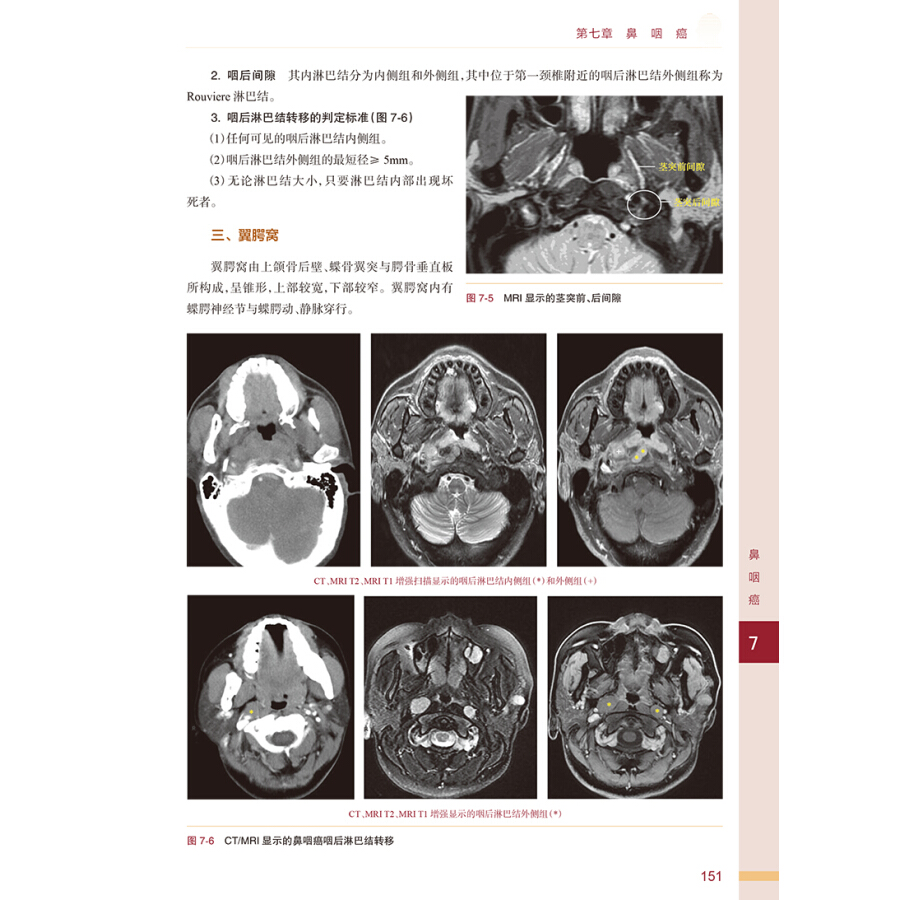

第七章 鼻咽癌 / 148

第一节 应用解剖 / 149